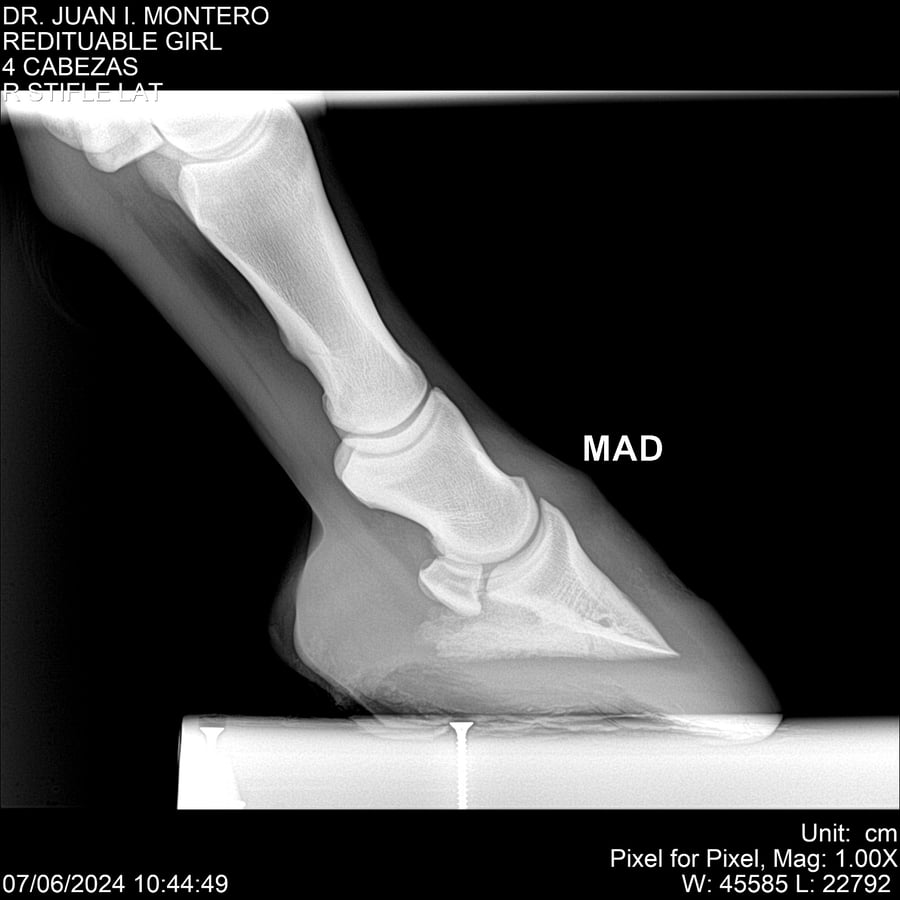

LOTE 19, REDITUABLE GIRL Lote Anterior Volver al remate Lote Siguiente Ficha Contacto Montevideo - Ficha del Lote Identificador: #281096 Categoría: Yeguarizos Montevideo - 79 Visualizaciones ClicData Contacto Empresa: Abelenda N. R., Walter Hugo Nombre*: Teléfono* : E-mail* : Mensaje Enviar Registrese gratis Este contenido Exclusivo está disponible sólo para usuarios registrados Ingresar